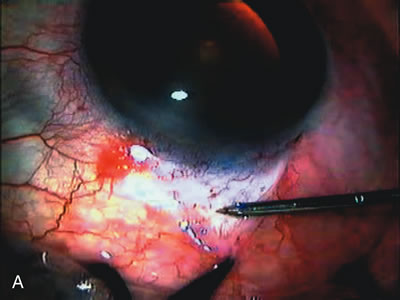

Fig. 1. The anatomic advantage of small incision cataract surgery for the glaucoma patient. A. Long-term bleb function with a large cataract incision is difficult to achieve with either ECCE-trabeculectomy or trabeculectomy followed later by ECCE. This bleb failed to form sufficiently when combined with large incision ECCE. The inflammation, bleeding, and long-term wound healing with stimulation of fibroblasts associated with this technique are more likely to cause bleb failure. In addition, the increased iris manipulation necessary to deliver the nucleus and subsequent iris repair adds to the long-term breakdown of the blood aqueous barrier. B and C. Two-site phacotrabeculectomy has the advantage of small incision cataract surgery combined with separate site trabeculectomy. The incision size is one third the size of the standard ECCE. The inflammation is less severe, and cataract wound healing is confined to the temporal area. Visual rehabilitation with phacoemulsification and foldable IOL is much faster. Phacoemulsification allows successful lens extraction even in the unfriendly environment of a smaller pupil compared with ECCE. The trabeculectomy is performed in an entirely different site, well away from the wound healing associated with temporal phacoemulsification. The likelihood of this filter functioning long-term is greater than with ECCE-trabeculectomy. D. The surgeon also has the option of single-site phacotrabeculectomy with foldable IOL. Both the lens extraction and trabeculectomy are performed through one small 3.5-mm limbal incision.

Fig. 3. Partial bleb failure following clear corneal phacoemulsification with foldable IOL. A. Preoperative bleb appearance prior to temporal lens extraction. Preoperative IOP was 12 mm Hg on no antiglaucoma medications. Time from 5-FU trabeculectomy surgery to lens extraction was one year. B. Bleb appearance 2 months after clear corneal cataract surgery with topical anesthesia. Following lens extraction, increased vascularity was noted along with decreased size of the filtering bleb. IOP increased to 20 mm Hg as early as 2 weeks after surgery, necessitating topical antiglaucoma therapy. C. High magnification view of bleb before lens extraction demonstrates diffuse pale bleb. D. High magnification view of bleb 2 months after surgery. There are vessels surrounding the nasal side of the bleb and the overall bleb size is smaller.